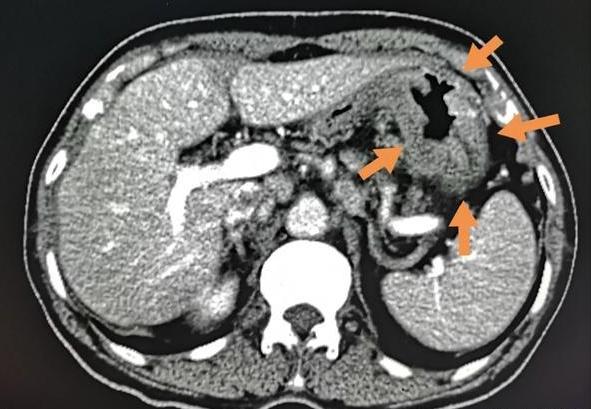

胃镜活检为中、低分化腺癌,CT显示胃窦壁广泛增厚(箭头所示)。

因为来的有点晚,肿瘤已经比较大了,只能做全胃切除。目前已经5个多月了,恢复还不错!